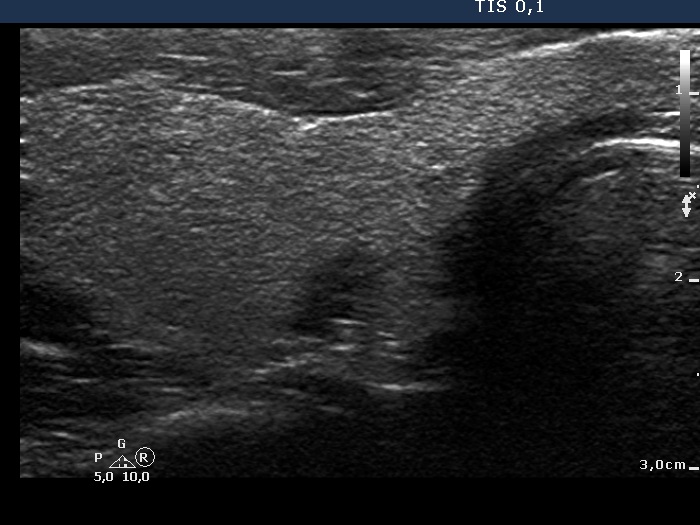

Ultrasonography. The thyroid was echonormal. There was a discrete, deeply hypoechoic area in the dorsal part of the right lobe. Although the dimensions were only 4x7x5 mm, width, depth, length, respectively, the lesion would correspond to a TIRADS 5 lesion because it was very hypoechoic and presented with irregular shape. However, color Doppler mode proved that this was indeed a vessel and not a solid thyroid tissue. The left lobe had a minimally hypoechoic lesion which largest diameter was 9 mm.